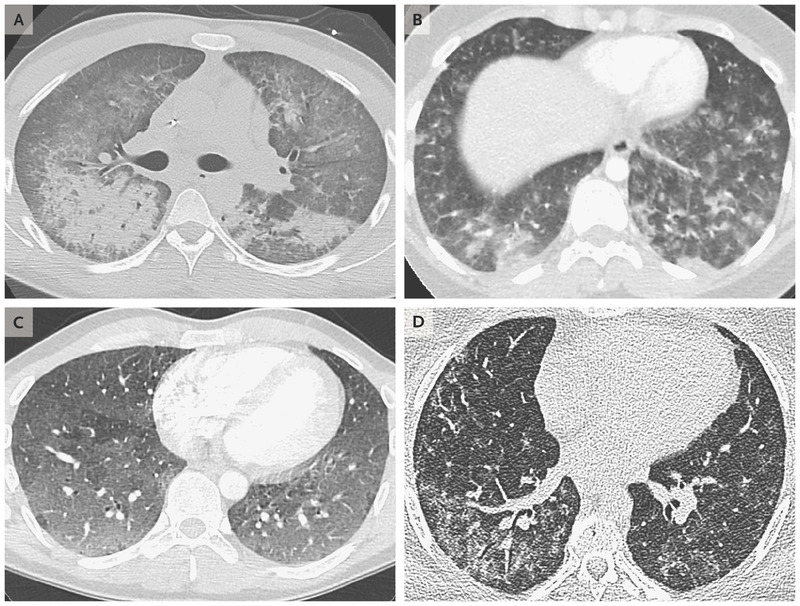

- 9/11現在、電子たばこによって深刻な肺疾患による死亡者が6人

- 33州450件に及ぶ肺疾患が報告されている